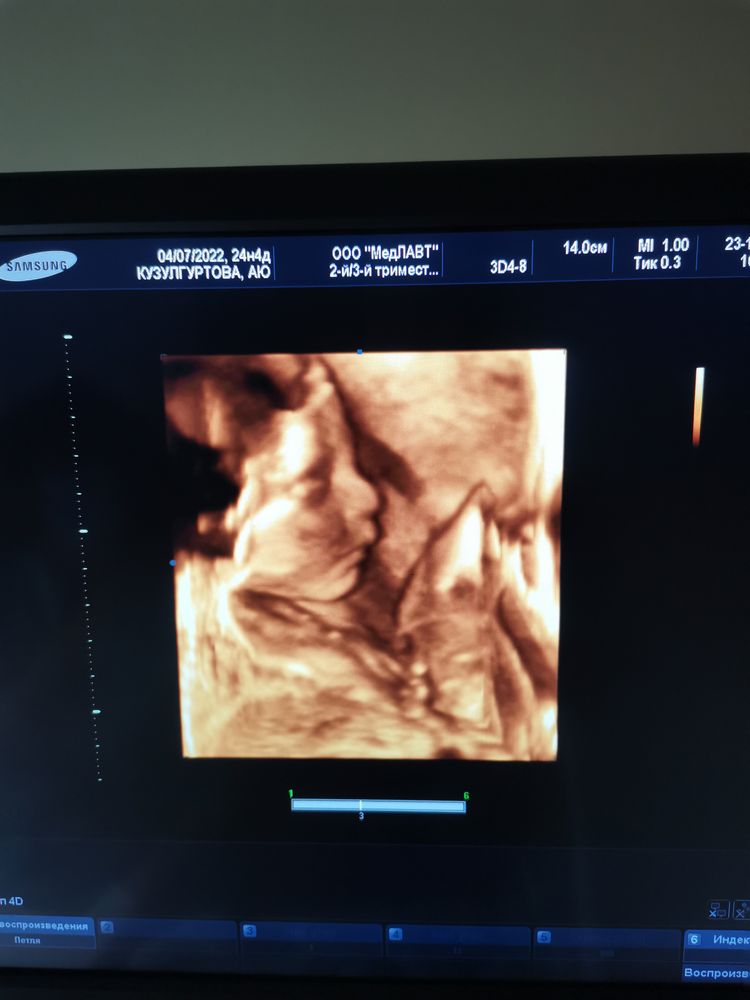

Растём!) перед НГ сходила на цервикометрию, всё хорошо, отменяю одну дозу утрожестана. Заодно врач посмотрела сыночка, весим уже 841гр, остальные параметры в норме. Даже попробовали в 3д посмотреть, немного получилось (фото ниже🥰). Общая прибавка +9кг. Отёков нет. Умудрилась неделю назад заболеть, началось с горла, потом сухой раздирающий кашель до болей в животе и температурой 37,8 один день. Обычный терапевт, кроме промывания горла аквамарисом, не назначила вообще ничего😔, пришлось идти к платному, там уже назначили адекватное лечение. И, да, молоко+мед+масло реально помогают. Это в кратце), а вообще, бесплатная медицина и неопытные врачи, это отдельная тема. Теперь счастливая и спокойная буду готовиться к праздникам 🎄🌸.

Какой пышный пузик для такого срока :) 3д очень милое, и не похожее на другие (мне чаше всего кажется, что везде одинаковые)